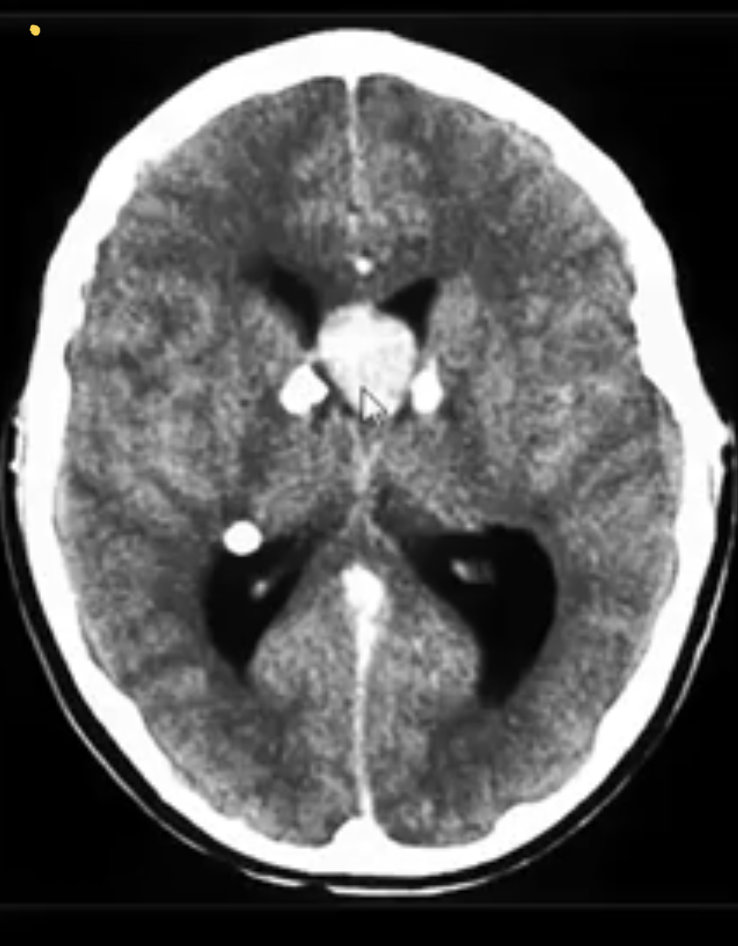

AQUEDUCTAL STENOSIS:

-acquired causes?

Extrinsic compression

tectal plate glioma / pineal tumour / posterior fossa tumour / cerebral vascular malformation

Intrinsic stenosis

infection: meningitis/ventriculitis

subarachnoid haemorrhage (SAH)

-congenital causes?

congenital causes:

aqueductal webs or diaphragms / gliosis